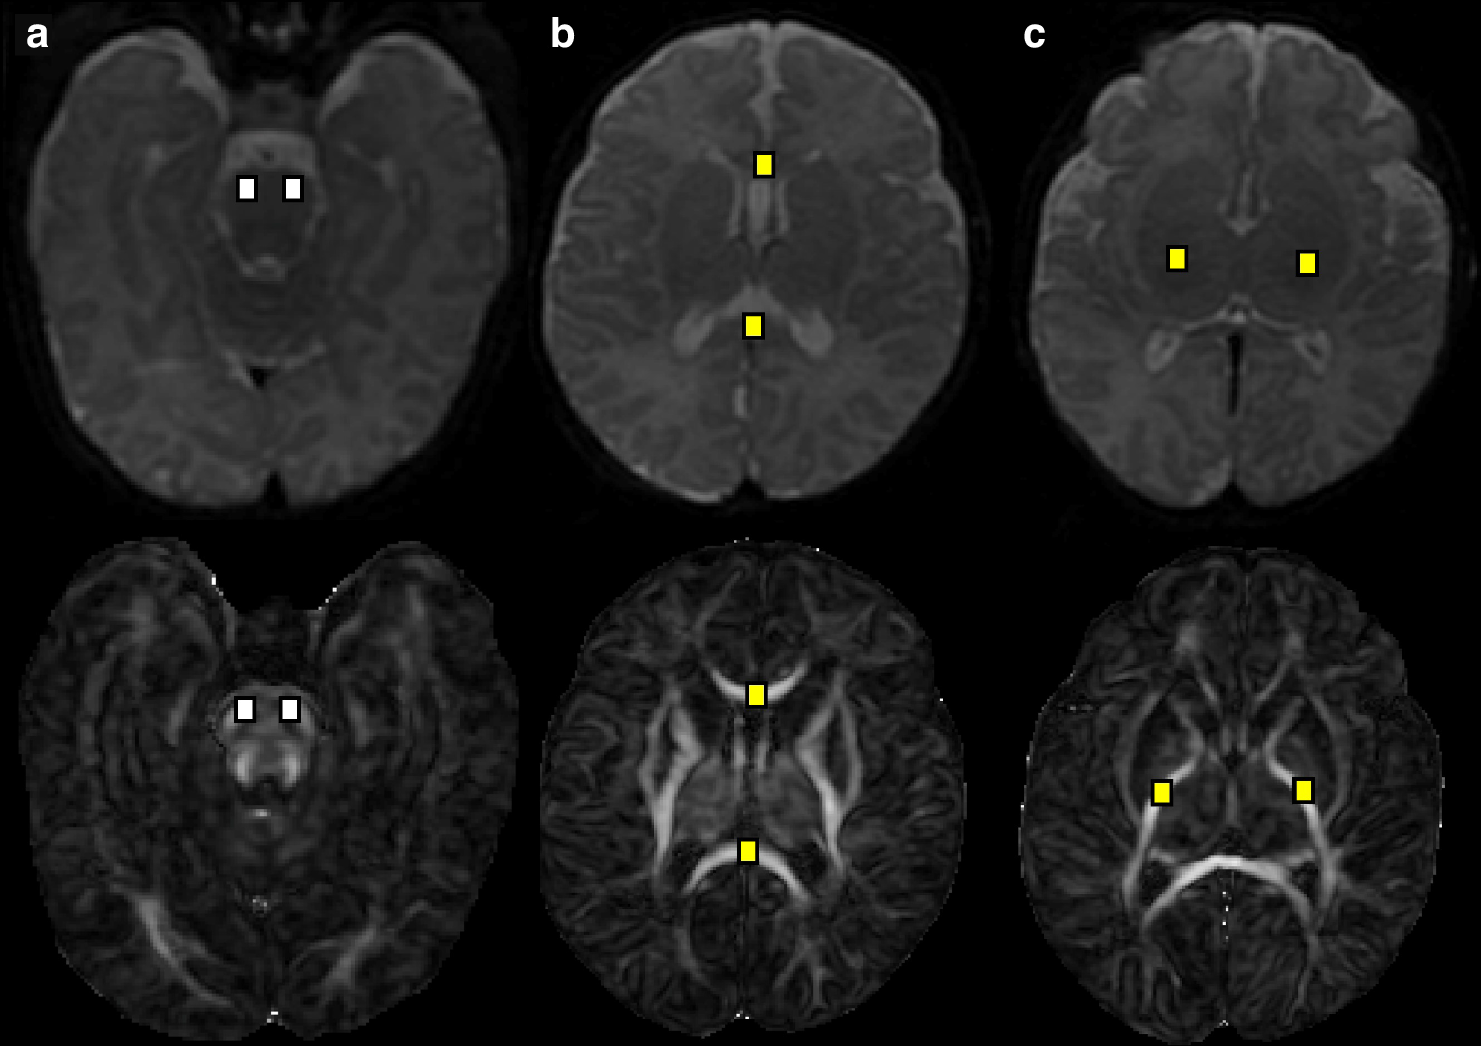

Fig. 3: Term-equivalent axial DTI B0 images and parametric maps with white matter tracts demonstrating significant differences between maternal milk and donor human milk (white) or preterm formula-fed (yellow) infants.

a Brainstem (pons), b corpus callosum, c posterior limb of internal capsule.